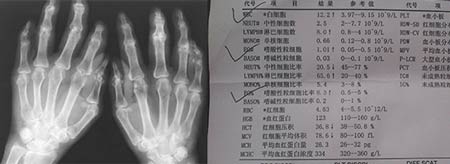

(图:夏先生初到院时双手X光检查档案)

HD-热层析检测:发现患者双膝关节组织炎症明显,手指关节出现炎性反应,体积有增大趋势。

常规检查:双手指远端指间关节海伯登结节,关节僵硬,握拳无力。双膝肿胀Ⅲ°,皮温高,浮髌试验(+),屈100°伸-20°。

实验室检查:RF(+)(类风湿因子)血沉65mm/H,C-反应蛋白20mg/L。余指标正常。

(图:夏先生复诊时双手X光对比)

三个疗程结束后来院复诊检查,夏先生得知血常规白细胞,类风湿因子,C反应蛋白等等检查都符合临床上的健康标准。经陈建春主任问询,夏先生自述自从治疗后关节肿胀、疼痛感明显的减轻了,行动也自如了。